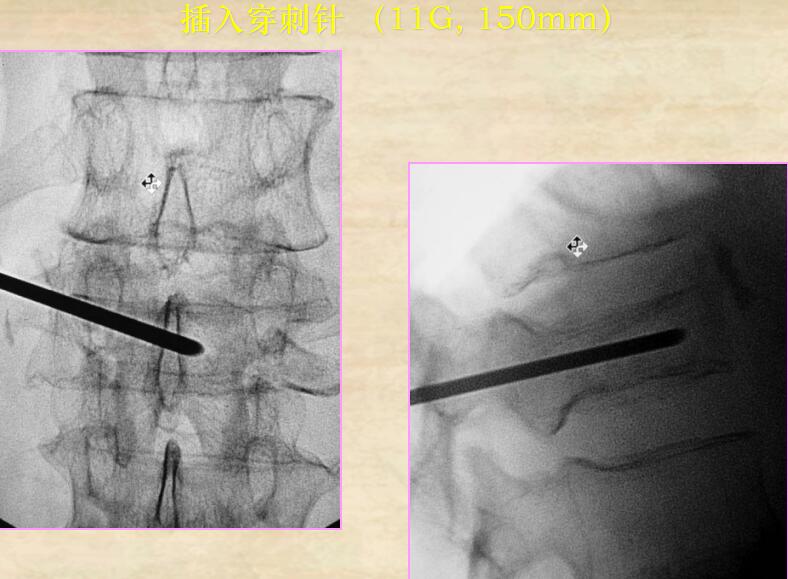

1、插入穿刺針